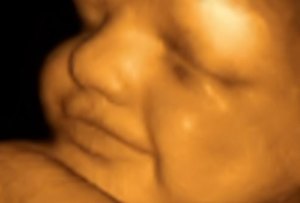

Fetus at 28 Weeks

All pictures came from:  http://www.webmd.com/baby/slideshow-fetal-development